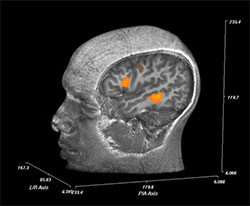

Figure 2: Pre-surgical language mapping with fMRI.